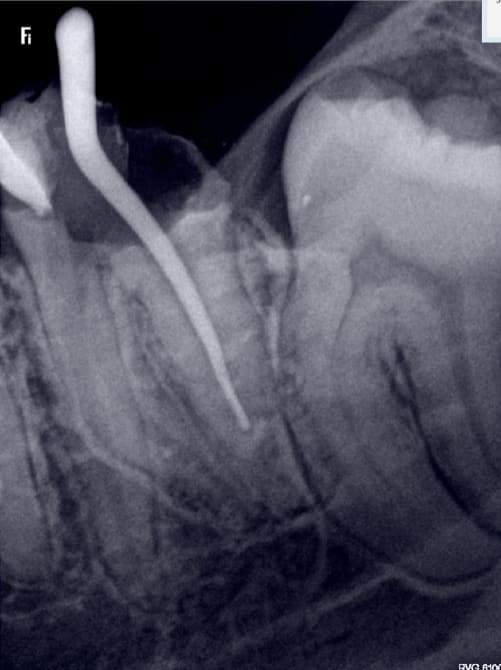

Et d'une. RTE s'il vous plait. -)

Capture d écran 2017 02 02 18.52 - Eugenol